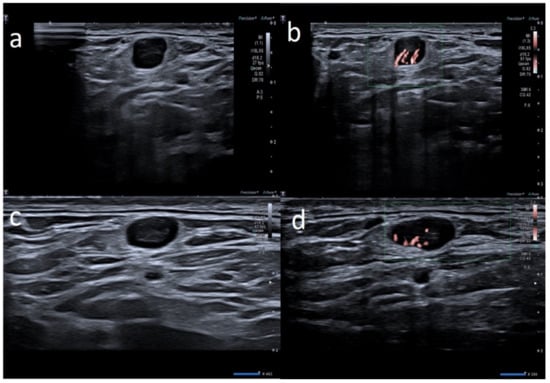

| M | 64 | Pfizer | Supraclavicular ipsilateral to vaccine injection | Occasional autopalpation 2 weeks after second dose vaccine | None | 2 | Around 1.0 cm | Ovular | Assimetric cortical thickening with hilum evidence | Stiffness similar to surrounding tissue | Normal | Unnecessary other follow-up |

| M | 60 | Pfizer | Supraclavicular ipsilateral to vaccine injection | Occasional autopalpation 12 days after second dose vaccine | None | 2 | Around 1.0 cm | Ovular | Simmetric cortical thickening with normal hilum | Stiffness similar to surrounding tissue | Central and peripheral vascular signals | Unnecessary other follow-up |

| M | 57 | Pfizer | Axillary ipsilateral to vaccine injection | Occasional autopalpation 2 weeks after second dose vaccine | Kidney cancer 4 years ago | 2 | Around 1.0 cm | Ovular | Asimmetric cortical thickening with hilum evidence | Stiffness similar to surrounding tissue | Normal | Normalized to 30 days |

| M | 59 | Astrazeneca | Supraclavicular ipsilateral to vaccine injection | Occasionally, autopalpation 4 days after second dose vaccine | None | 2 | 0.7 and 1.2 cm | Ovular | Asimetric cortical thickening with hilum evidence | Stiffness similar to surrounding tissue | Normal | Unnecessary other follow-up |